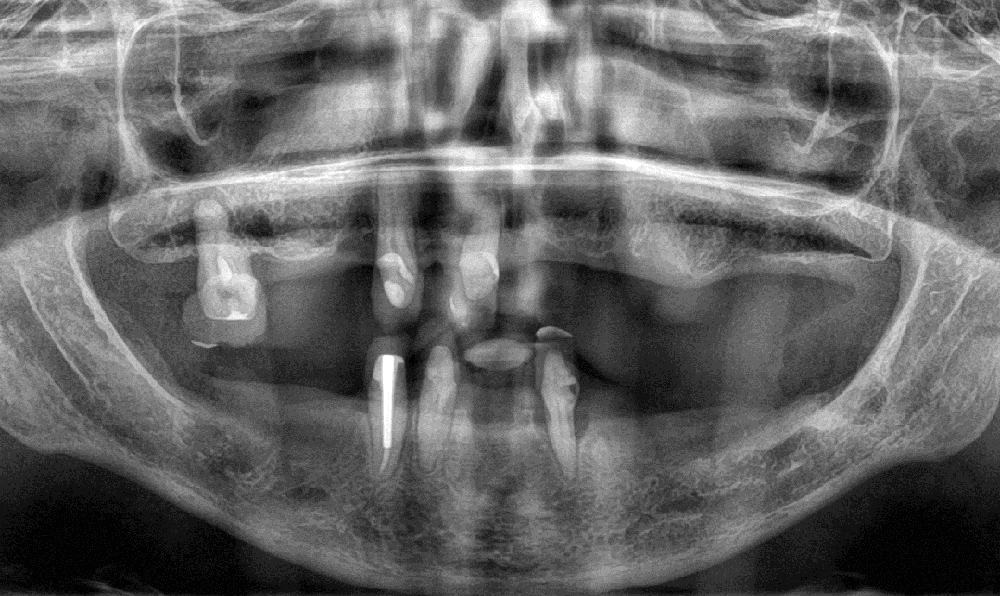

Befund

Die Patientin hatte jeweils drei verbliebene Zähne im Ober- und Unterkiefer, die weit aufgefächert, gelockert und sekundär gewandert waren. Mit schlecht sitzenden Modellgussprothesen hatte sie Schwierigkeiten beim Essen und mied soziale Kontakte. Der Wunsch war festsitzender Zahnersatz mit Implantaten sowie die Wiederherstellung von Funktion und Ästhetik. Nach gründlicher Abwägung aller relevanten Parameter wurde mit der Patientin entschieden, dass die restlichen Zähne nicht erhaltungswürdig sind und eine festsitzende, implantatgetragene Sofortversorgung, die beste Behandlungsoption darstellt. Im DVT war sehr spongiöser Knochen erkennbar. Deshalb wurden sechs Implantate geplant, um die Gesamtstabilität zu erhöhen, falls intraoperativ die gewünschten Eindrehwerte über 35 N/cm nicht erreichbar wären.